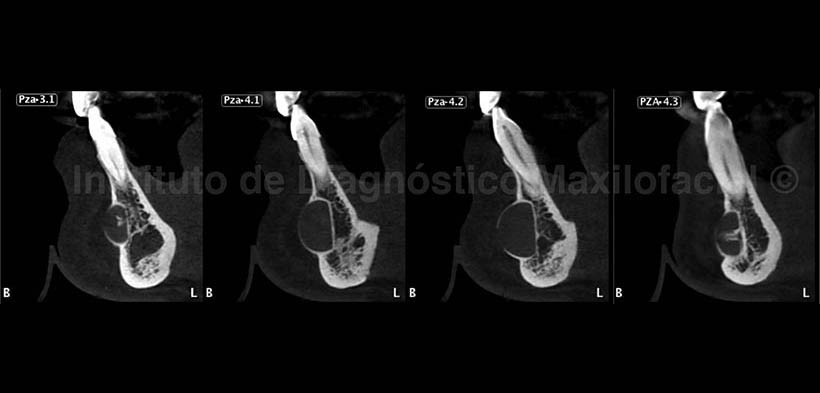

A la evaluación con tomografía volumétrica, en la reconstrucción panorámica (Fig. 2) confirmamos la presencia de una imagen hipodensa de limites definidos y corticalizados a nivel de la zona media del maxilar inferior compatible con un implante de mentón.

En los cortes transaxiales (Fig. 3) se aprecia la relación con las piezas dentarias ya mencionadas, además de la corticalizacion del implante debido a la proliferación periostal de la tabla vestibular, y a nivel de las piezas 3.1 y 4.3 se observan imágenes hiperdensas correspondientes a probables secuelas de tornillos de fijación del implante. Nótese la imagen hiperdensa a nivel apical de la pieza 4.2 compatible con osteoesclerosis.